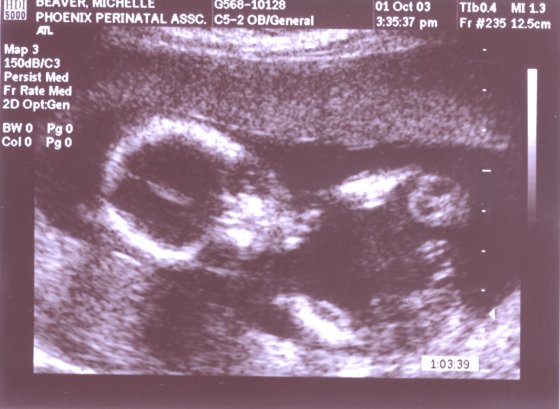

Full head again, this time left hand up under chin.